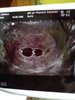

Dziękujemy bardzo jak narazie czujemy się świetnie poza małymi dolegliwościami takimi jak bezsenność i ból pleców to jest w porządku.Jejku ale super!!!! Ciąża bliźniacza [emoji173]️ Bóg was błogosławił podwójnie za tamta stratę. Trzymajcie sie w spokoju. Gratuluje podwójnie! [emoji177]

Gratulacje!Pieknie! Mamy bliźniaki na wątku![]()